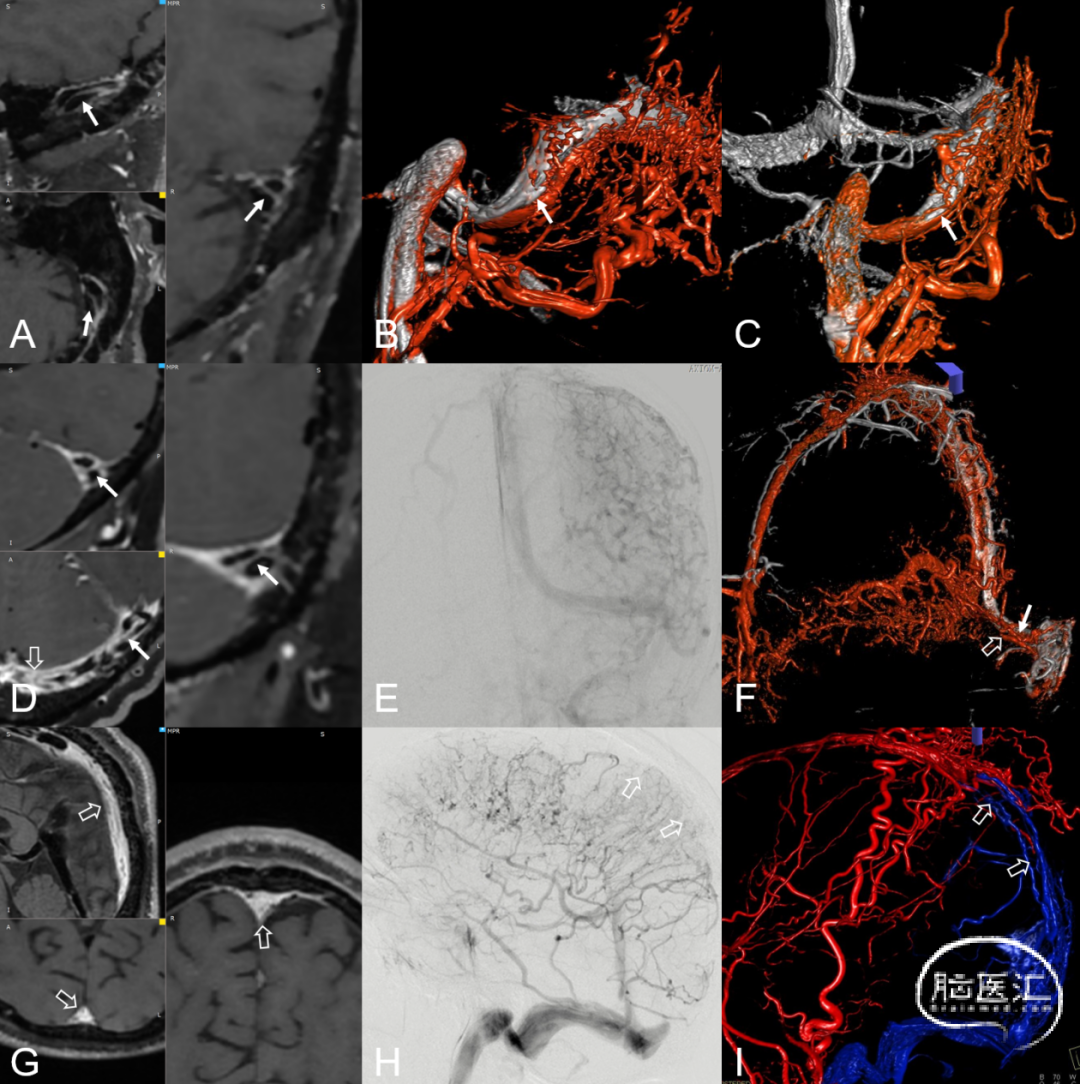

图2. 窦型DAVF的血管构筑与硬膜血管汇集区。侧窦区窦型DAVF,起自硬膜固有静脉系统向横-乙交界区汇聚(A-C)

2.桥静脉型硬脑膜动静脉瘘(bridging vein type DAVF, BV-DAVF),即动-静脉移行起自硬膜固有静脉,经桥静脉硬膜内段向软膜静脉逆流。由于桥静脉向静脉窦直接引流受阻,动静脉瘘无法直接进入静脉窦,而通过侧枝吻合进入邻近静脉窦。影像学表现为桥静脉-软膜静脉早显,并早于静脉窦显影(图3)。

图3. 桥静脉型DAVF的血管构筑。侧窦区桥静脉型DAVF的起点位于桥静脉硬膜内段,由MMA(黑箭)供血,向软膜静脉逆流(A)。同侧乙状窦(双白箭)晚于桥静脉-软膜静脉间接显影(B)。脑静脉窦期显示静脉窦血流通畅,侧裂浅静脉回流被DAVF竞争性抑制(C)

3.板障-导静脉型硬脑膜动静脉瘘(diploic-emissary vein type DAVF, DEV-DAVF),即动-静脉移行起自骨内的板障静脉或穿骨的导静脉,向静脉窦或浅表静脉系统引流。影像学表现为骨内静脉结构早显,并早于静脉窦显影(图4)。

图4. 骨内静脉系统与板障-导静脉型DAVF。板障-导静脉型DAVF,骨内的初级静脉(A白箭)汇聚至板障静脉SP(B双白箭),经蝶顶窦-海绵窦向眼静脉侧裂浅、深静脉逆流(C)。

图7. 右侧枕动脉 (Occipital artery, OA) 参与DAVF供血,轴位最大信号投影 (Maximum intensity projection, MIP) 图发现右侧OA (箭头示) 较左侧OA (细箭示) 直径增宽、信号明显增强 (A) ;3D TOF血管重建,剪除周围血管后可以清晰显示右侧OA明显增粗 (B箭头示) ;右侧枕动脉造影证实右侧OA参与DAVF供血 (C箭头示)。左侧脑膜垂体干 (Meningo-hypophyseal trunk, MHT) 参与DAVF供血,轴位MIP图发现左侧MHT直径明显增宽、信号明显增强 (D箭头示) ;3D TOF血管重建清晰显示左侧MHT明显增粗 (E箭头示) 。左侧颈内动脉造影证实左侧MHT参与DAVF供血 (F箭头示) 。右侧脑膜后动脉 (Posterior meningeal artery, PMA) 参与DAVF供血,轴位MIP图发现右侧PMA直径明显增宽信号增强 (G箭头示) ;3D TOF血管重建显示右侧PMA明显增粗 (H箭头示) 。右侧椎动脉造影证实右侧PMA参与DAVF供血 (I箭头示) 。

图8. 识别共同静脉端。3D TOF-MRA轴位可以识别左侧侧窦区DAVF弥散引流静脉集中向左侧横-乙状窦交界区 (Common collector, 共同静脉端,A箭示) 及窦汇区汇流 (共同静脉端,B箭示) 。DSA造影证实DAVF弥散,向横乙交界区及窦汇区附近汇流 (共同静脉端,C-F箭示) 。

图11. SWI显示右侧侧窦高信号-动静脉分流 (A白箭) ,提示硬脑膜动静脉瘘发生部位在右侧侧窦;直窦高信号提示硬脑膜动静脉瘘向直窦逆流 (B空箭) ,左侧小脑高信号周围低信号环 (B白环) ,提示颅内出血;瘀滞静脉低信号 (C黑箭) 。DSA造影可见右侧侧窦区硬脑膜动静脉瘘 (A、B白箭) ,向横窦及直窦逆流 (D、E空箭) ;静脉瘀滞 (F黑箭) 。

MR-VWI在DAVF的应用发现自发性破裂的血管壁表现出明显强化的特点。血管壁强化与出血具有一定的相关性,有关强化机制可能是动脉血冲击引起的静脉壁炎性改变,导致局部管壁脆弱而促使血管容易破裂出血。MR-VWI亦可以显示静脉窦腔内结构,提示有无静脉窦血栓,亦可以评估经静脉EVT手术路径的可行性,进而辅助制定手术策略。

图12. 高分辨率管壁成像及DSA图像对DAVF静脉窦腔内结构特征评估。左侧侧窦窦内可见静脉脊结构 (A细箭) 。3D融合DSA (颈内动脉静脉期旋转造影+颈外动脉旋转造影) 证实了静脉脊的存在,静脉脊 (B、C细箭) 将乙状窦分成了两部分,上部负责正常的引流功能,下部为DAVF引流出口。左侧侧窦见静脉脊 (D细箭) 及血栓 (D空箭) 。DSA证实了静脉脊 (E、F细箭) 及血栓 (E、F空箭) 存在。静脉窦内血栓形成静脉脊形态无法分辨 (G空箭) 。DSA证实血栓 (H、I空箭) 存在

图13. DAVF逆流皮层静脉及瘀滞静脉的高分辨率管壁成像及DSA图像。高分辨率管壁成像显示逆流皮层静脉壁 (A、B白箭) 。DSA证实逆流皮层静脉 (E、F白箭) 。高分辨率管壁成像见瘀滞静脉壁 (C、D白粗箭) 。DSA证实此静脉为瘀滞静脉 (G、H白粗箭)